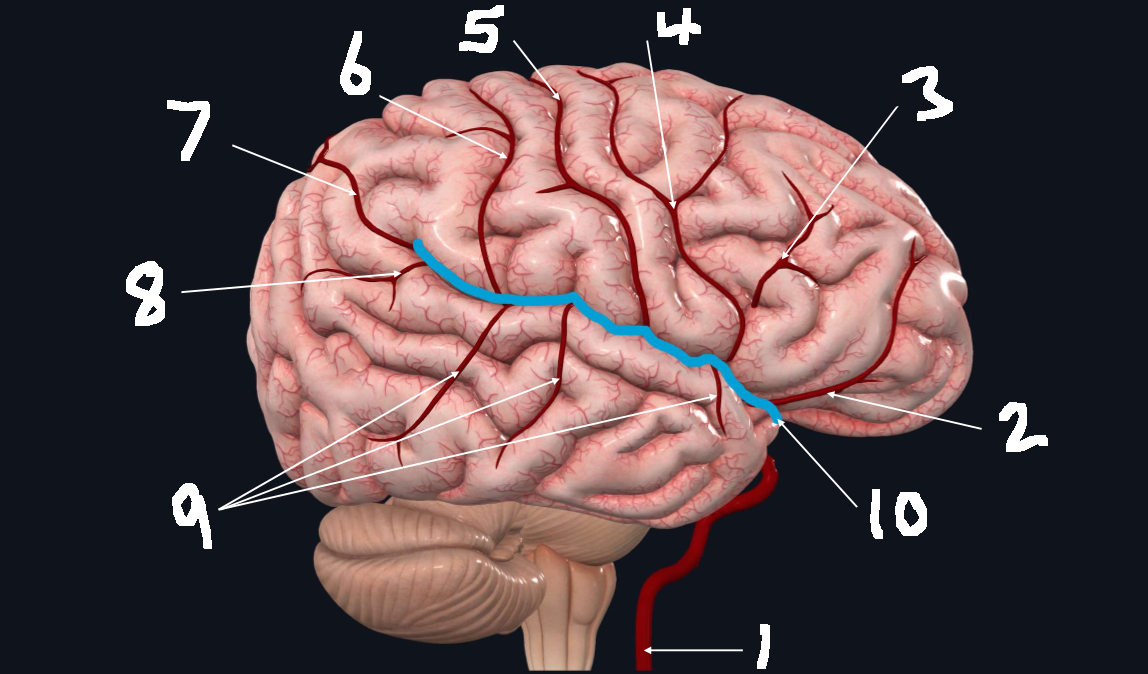

What is 1?

internal carotid artery

What is 2?

orbitofrontal artery

What is 3?

prefrontal artery

What is 4?

precentral artery

What is 5?

central artery

What is 6?

postcentral artery

What is 7?

posterior parietal artery

What is 8?

angular artery

What is 9?

temporal arteries (anterior, middle, posterior)

What is 10?

lateral cerebral fissure